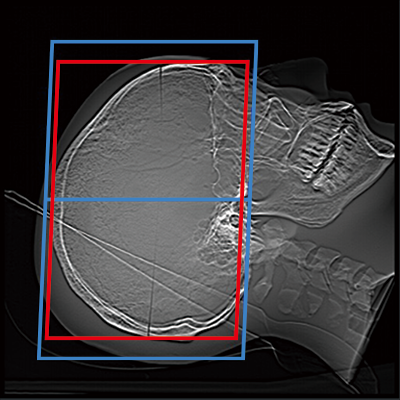

赤:自動設定された位置、青:自動設定された位置+マージン設定の位置

頭部(OM Line)